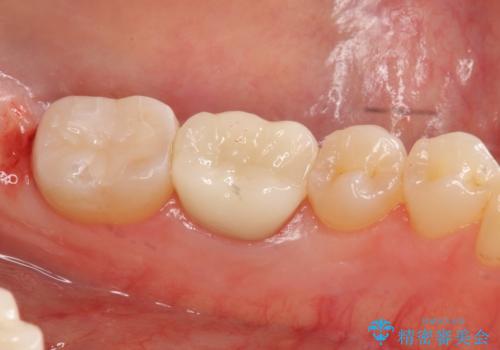

手術後、きちんとマージンラインが歯肉の上に来た状態で、セラミックインレー修復を行いました。

また、左下6番は専門医(銀座院院長 Dr.林)による再根管治療を行いました。

- 38万円(左下7:歯周外科処置5万円、セラミックインレー7万円 左下6:精密根管治療(再治療・専門医による)13万円、ファイバーコア2万円、ジルコニアクラウン10万円、仮歯1万円)費用は治療当時の料金となります